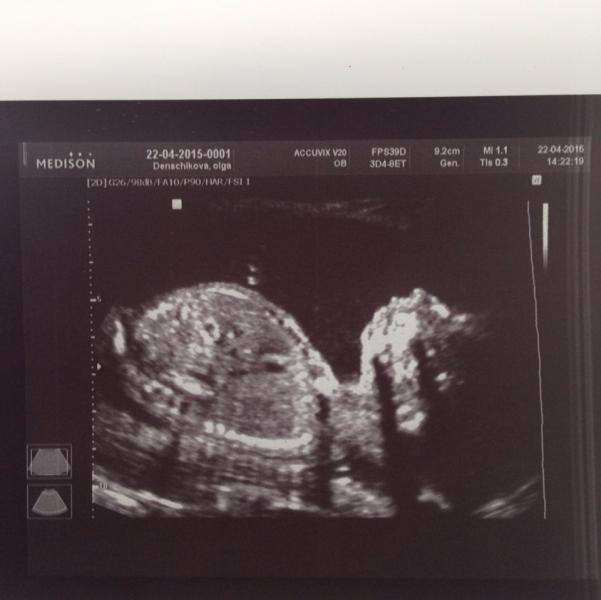

Девчули, мамули 😻😻😻были сегодня на скрининге 2м!!! Нам 19недель и два дня, вес 270 гр и у нас девчуля-красатуля) так пока называем малышку🙏🙏🙏вот теперь дождались того времени когда можно начинать плавно подготавливать к новому человечку нашему👼лежу счастливая,довольная)! Вот для многих второй семестр это и есть счастливая беременность!!! Первый для меня был ад адский😆😆как будто в другом мире жила)! Узи делала в северо западном медицинском центре ! По Питеру их много вроде, мы на савушкина ! Очен...